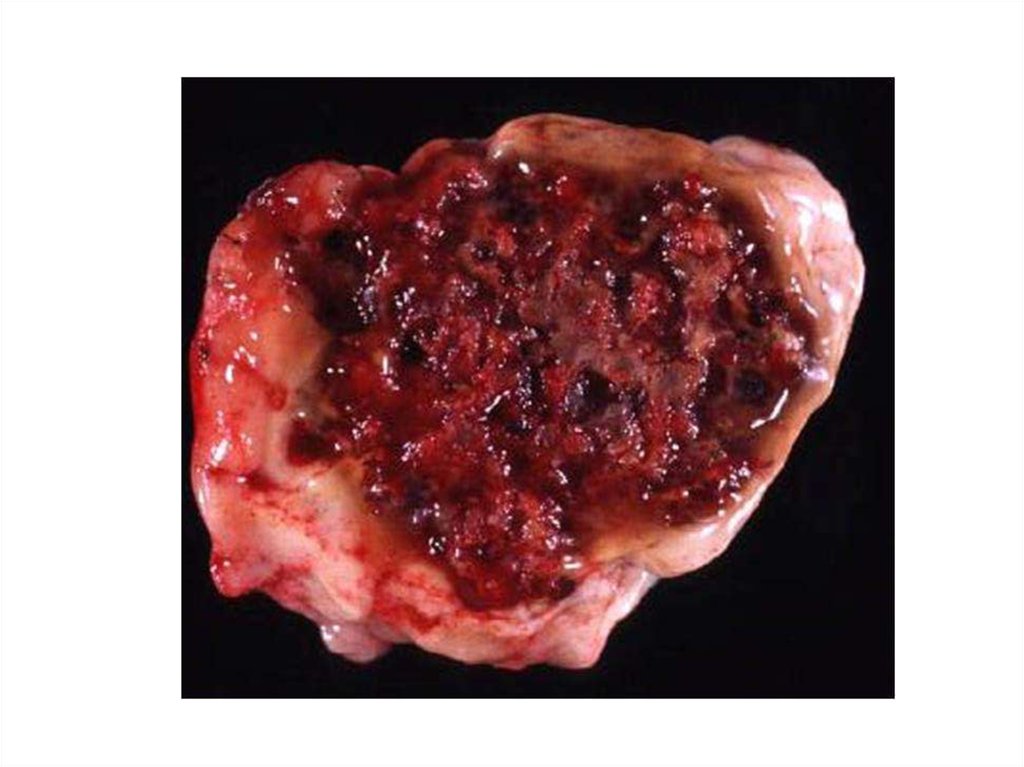

46. Церебральная кавернозная венозная мальформация (кавернозная гемангиома)

48 – 86% - в полушариях

5 – 13% сосудистых мальформаций ЦНС

Манифестирует в 40-60 лет

Клиническая картина: обмороки (60%),

неврологический дефицит (50%),

кровоизлияния (20%), гидроцефалия

(50%)

47.

48.

49.